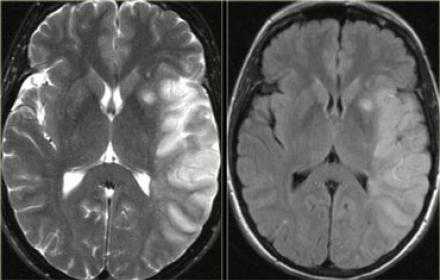

Магнитно-резонансная томография

Т2-взвешенные изображения

Высокая интенсивность сигнала на Т2-ВИ не проявляется в первые 8 часов после начала ишемического инсульта. Гиперинтенсивность характерна для хронической фазы, достигая максимума в подострый период. Феномен затуманивания на МРТ может визуализироваться спустя 1-4 недели после инсульта с пиком, приходящимся на 2-3 неделю, он проявляется как изоинтенсивная относительно ГМ область, которая, как считается, является следствием инфильтрации зоны инфаркта воспалительными клетками. При обширных поражениях может происходить утрата нормального потока сонной артерий с ипсилатеральной стороны на Т2-ВИ спустя 2 часа после возникновения симптомов.

FLAIR-изображения

Интенсивность сигнала на FLAIR-изображениях после инсульта варьирует. Большинство исследований показывает, что интенсивность сигнала на FLAIR-изображениях изменяется в первые 6-12 часов после появления симптомов. Оновременное наличие изменений на ДВИ и отсутствие таковых на FLAIR-изображениях указывает на инсульт возрастом менее 3(6) часов со специфичность (93%) и положительной прогностической ценностью (94%) [1].

На PD/T2WI и FLAIR выглядит гиперинтенсивно. На PD/T2WI и FLAIR последовательностях возможно диагностировать до 80% инфарктов впервые 24 часа, но впервые 2-4 часа после инсульта изображение также может быть неоднозначным. На PD/T2WI и FLAIR продемонстрировано гиперинтенсивность в районе левой средней мозговой артерии. Обратите внимание на вовлечение в процесс лентиформного ядра и островковой доли. Область с гиперинтенсивным сигналом на PD/T2WI и FLAIR соответствует гиподенсивной области на КТ, что в свою очередь прямой признак гибели клеток мозга.